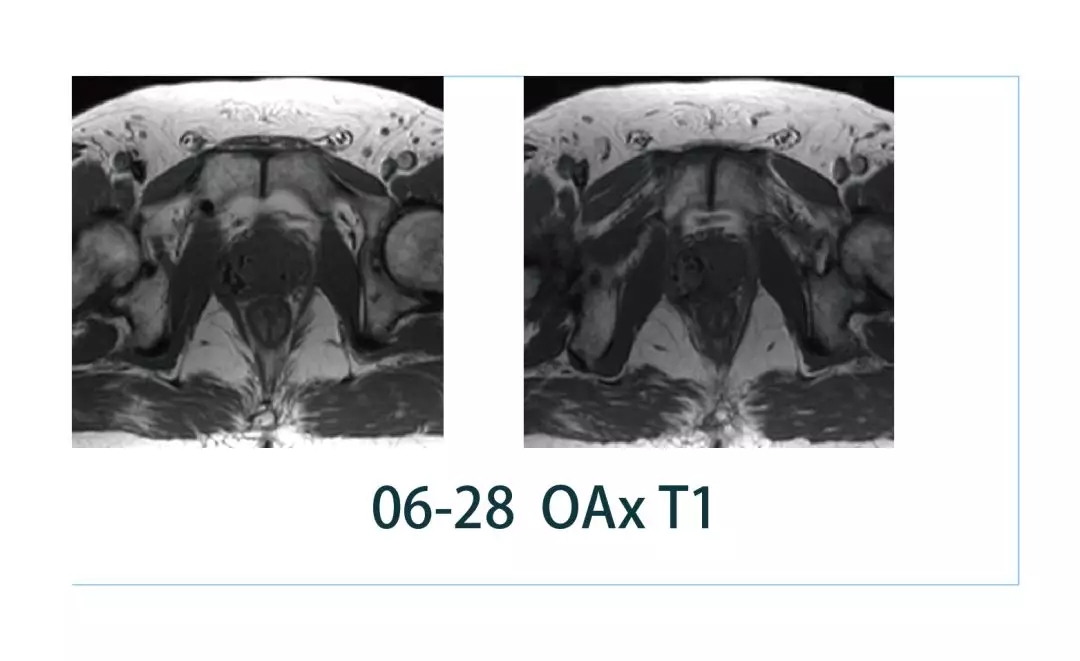

【朗润影像档案】20190308磁共振影像病例结果讨论